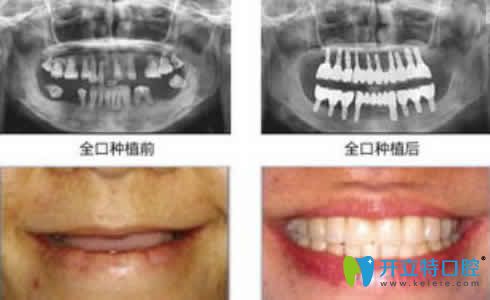

湛江致美口腔李啟森主任全口種植牙案例效果賞析:

湛江致美口腔李啟森全口種植牙案例效果